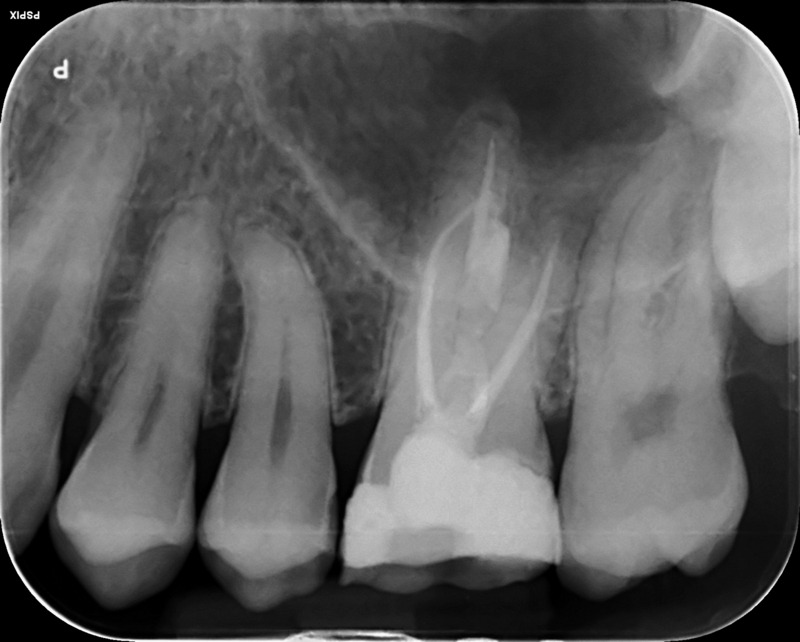

Fractured file removal and re-rct

Pre-op

Retrieved file

12 month review